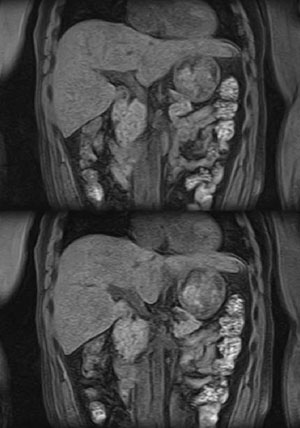

また,Enhanced Fat Freeは,さまざまなイメージングシーケンスと組み合わせることで幅広い臨床応用が可能となる。例えば,高速3D撮像法である“Quick3D’s”と組み合わせれば,高画質な全肝息止め造影撮像をルーチンで行える4)。この場合,広範囲にわたって高い脂肪抑制効果が得られるため,患者さんが手を下ろした楽な姿勢での脂肪抑制冠状断撮像が可能になる(図3)。

図3 Enhanced Fat Freeによる全肝の脂肪抑制冠状断